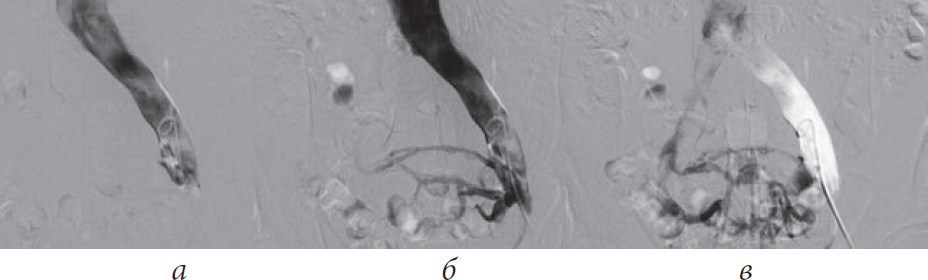

Рис. 5. Баллонная ангиопластика левой общей и левой наружной подвздошных вен пациента М., 39 лет, от 28.03.2017. Оперативный доступ из левой подколенной вены. Положение пациента на животе

Рис. 6. Имплантация одного стента в левую общую и левую наружную подвздошную вены пациента М., 39 лет, от 28.03.2017. Оперативный доступ из левой подколенной вены. Положение пациента на животе

Рис. 7. Постдилятация стентированного сегмента левой общей подвздошной вены пациента М., 39 лет, от 28.03.2017. Оперативный доступ из левой подколенной вены. Положение пациента на животе